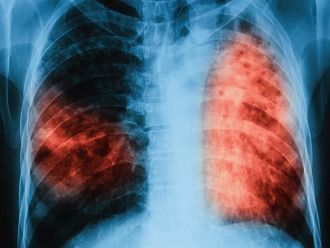

Заболеваемостта от туберкулоза е намаляла от 38 на 100 000 през 2008 г. до 18,4 на 100 000 през 2018 г. или в абсолютни цифри броят на заболелите от туберкулоза е намалял от 3 150 през 2008 г. на 1 358 през 2018 г. това стана ясно след провелата се заключителна среща по Програма „Подобряване на устойчивостта на Националната програма по туберкулоза“, финансирана от Глобалния фонд за борба срещу СПИН, туберкулоза и малария, съобщиха от здравното ведомство.